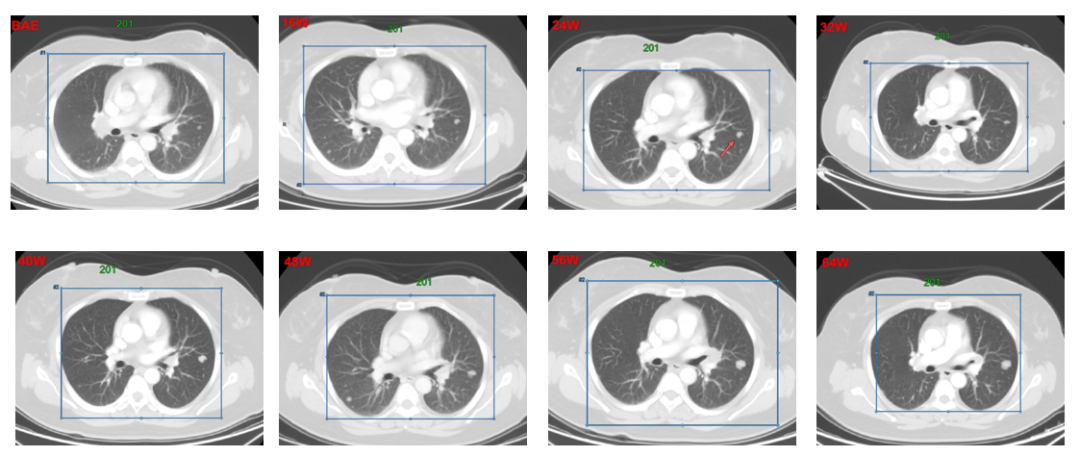

2015-06-18,接受肝左叶切除术,切缘阴性,术后恢复良好。2016.11,复查CT提示双肺结节增大,考虑双肺转移。2016-11-28,患者首次接受多纳非尼治疗(0.2g,每日两次口服),治疗初期,靶病灶显示轻微缩小,经评估为疾病稳定(SD),继续接受多纳非尼治疗,靶病灶持续缓解,经评估疗效达到部分缓解(PR)。整个治疗期间,独立审查委员会(IRC)评估的患者最佳疗效为SD,但研究者评估的最佳疗效为PR。同样,经IRC和研究者评估的无进展生存期(PFS)分别为为11.2个和15.1个月。

1号靶病灶为纵膈淋巴结,8w-40w,靶病灶整体被评为SD,48-64W整体被评为PR;

靶病灶影像学改变: